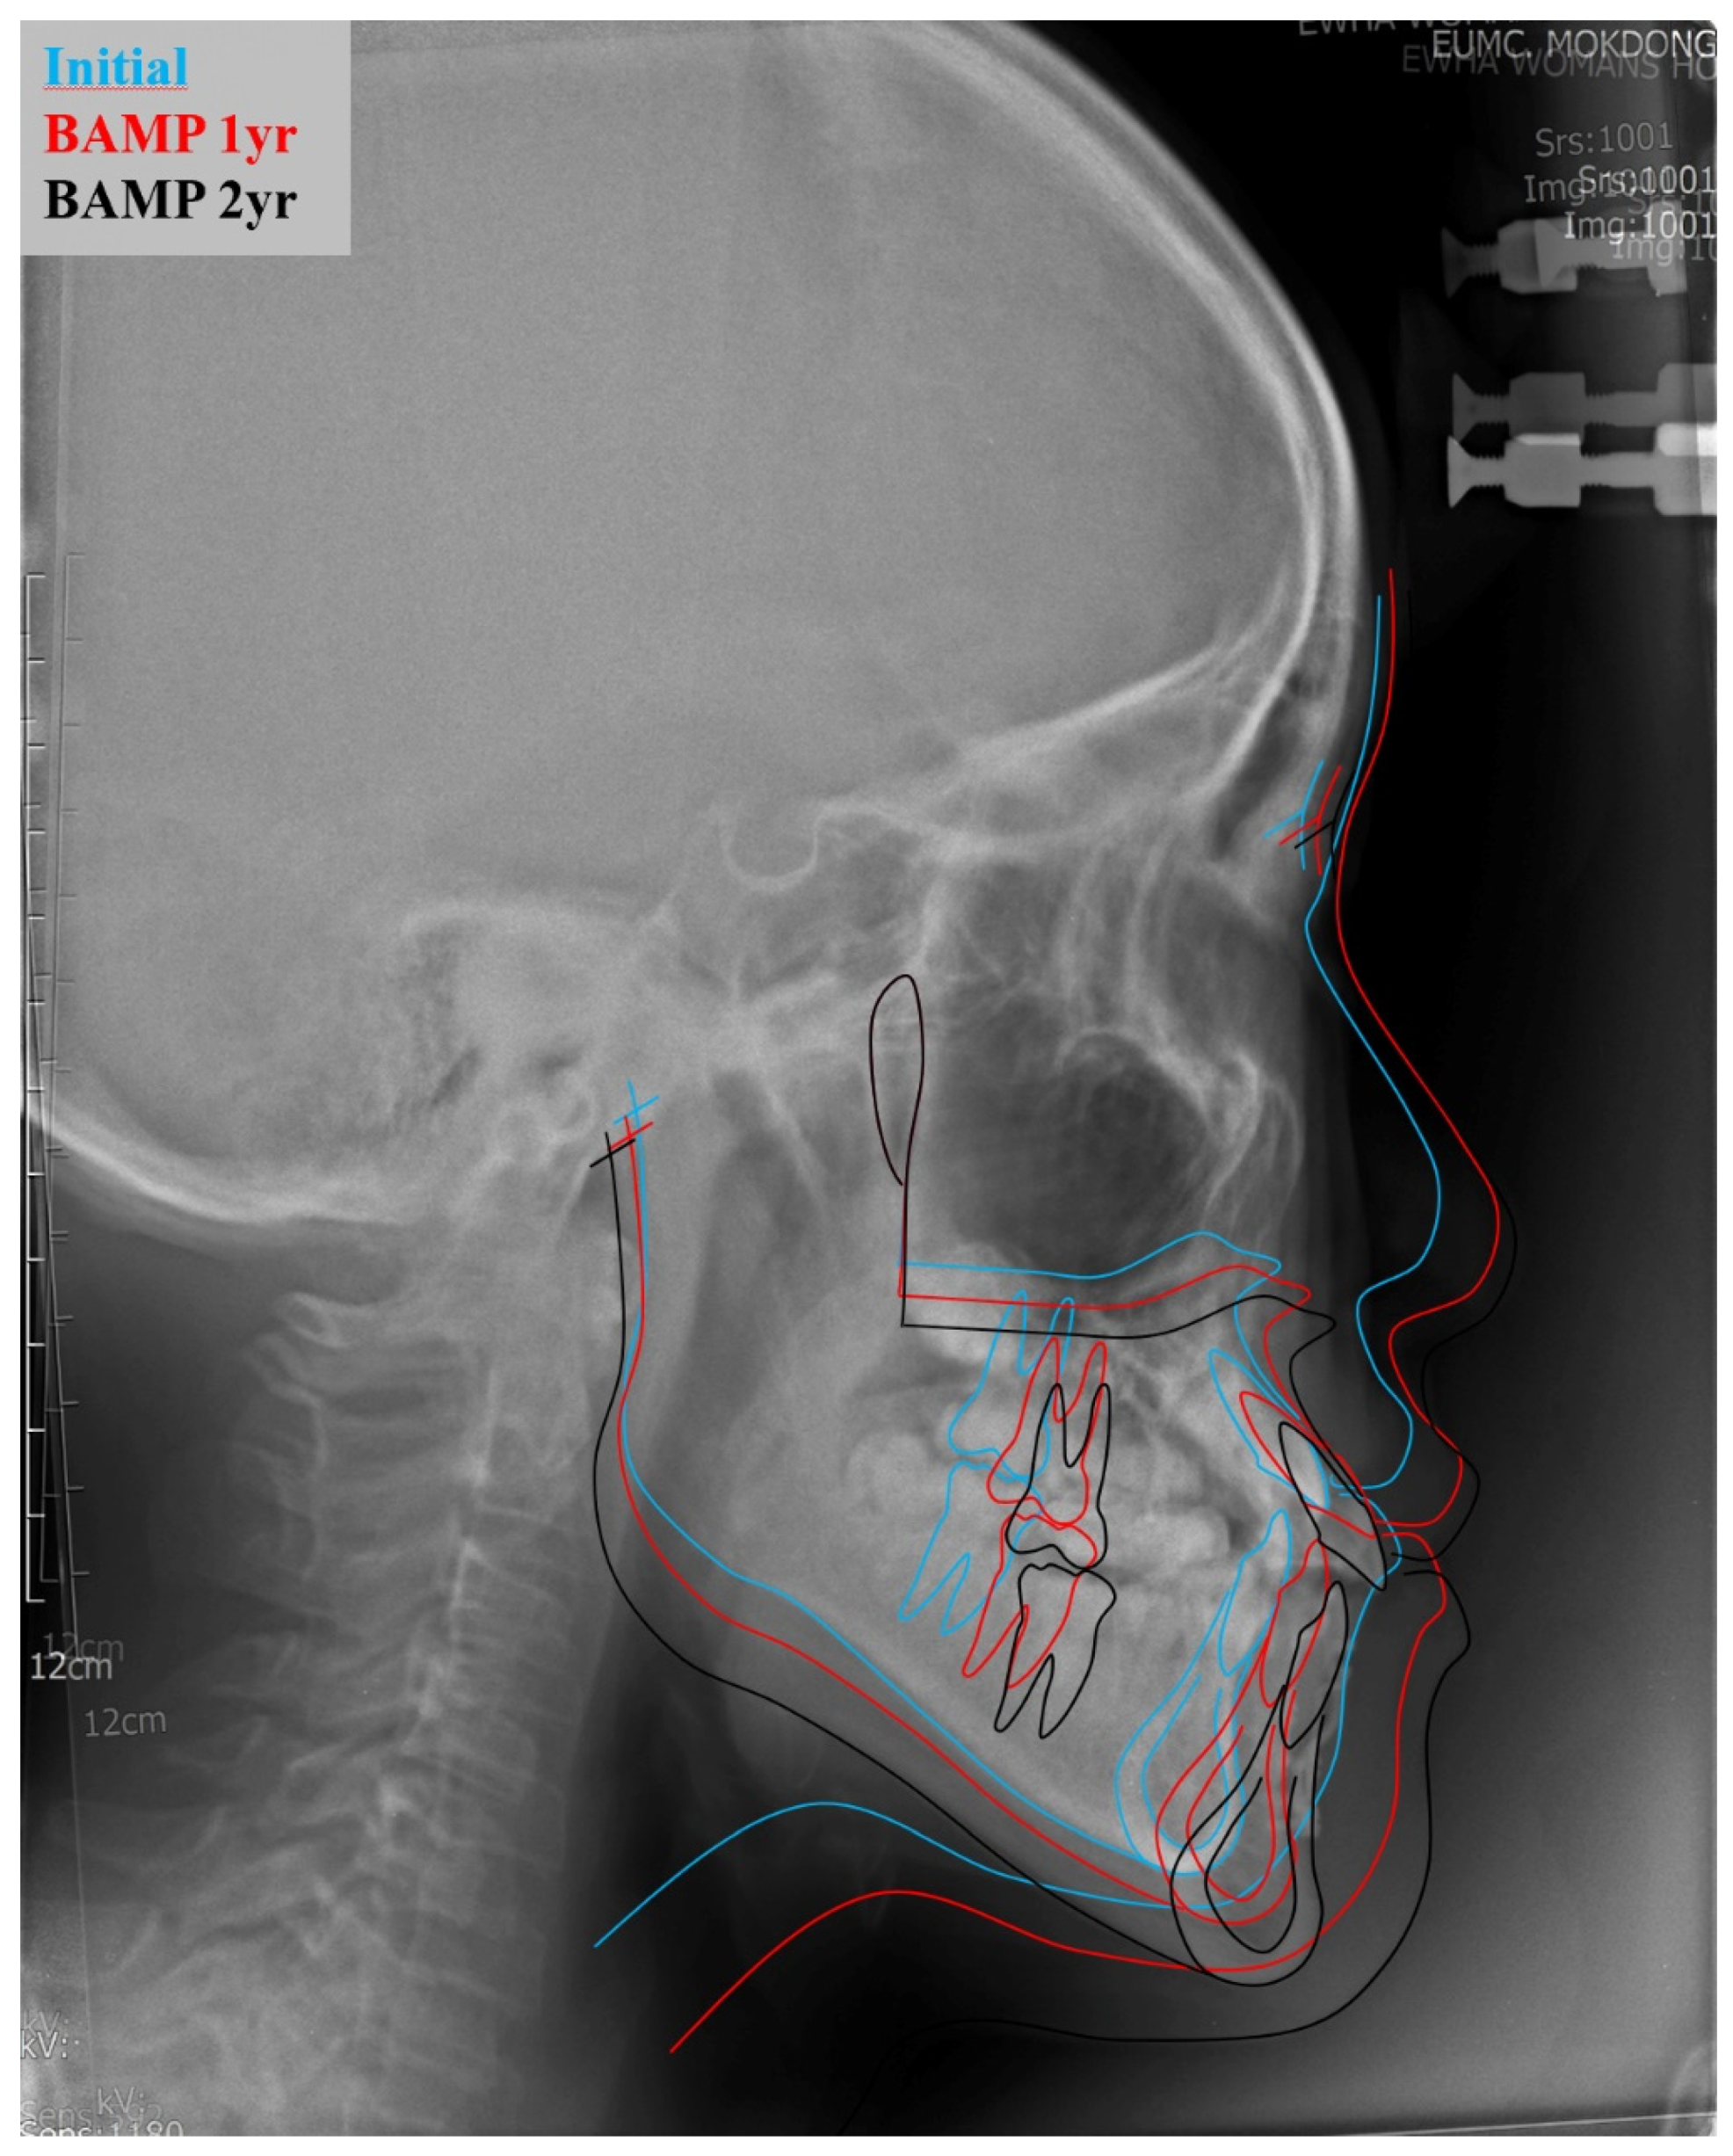

4. Case Presentation

| SNA | 81.6 (3.1) | 77.98 | 84.63 |

| SNB | 79.1 (3.0) | 82.54 | 85.72 |

| ANB difference | 2.4 (1.8) | −4.56 | −1.09 |

| Wits appraisal | −2.7 (2.4) | −7.52 | −3.26 |

| FMA | 29.63 (5.66) | 30.34 | 28.98 |

| SN-GoMe | 36 (4) | 37.1 | 32.72 |

| A point—N Perpend | 0.4 (2.3) | −5.37 | −1.86 |

| Facial Height Ratio | 65 (9) | 61.7 | 66.37 |

| Posterior Facial Height | 85 (5.5) | 76.84 | 90.76 |

| Anterior Facial Height | 127.4 (5.6) | 124.52 | 136.74 |

| U1 to SN | 107 (6) | 123.45 | 120.62 |

| IMPA | 95.9 (6.3) | 78.2 | 78.3 |

| Interincisal angle | 124 (8.3) | 121.2 | 128.32 |

| Upper Lip E-plane | 0.1 (2) | 0.44 | −1.58 |

| Lower Lip E-plane | 0.1 (2) | 2.69 | 0.26 |

| Nasolabial angle | 84.9 (5) | 93.86 | 101.9 |